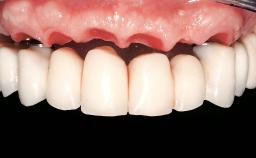

Conventional Loading of Eight Implants in the Maxilla and Final Restoration with a Full-Arch Gold-Ceramic FDP

A 35-year-old Caucasian female presenting with advanced periodontal disease involving both the maxillary and the mandibular dentition was referred for evaluation. The patient, a non-smoker in good general health, requested treatment for recurrent periodontal abscesses, tooth mobility, and discomfort during chewing, as well as restoration of her missing teeth with a fixed prosthesis to improve mastication and esthetics. All residual maxillary teeth exhibited plaque deposits, deep pockets, bleeding on probing, and class III mobility and were evaluated as hopeless. All residual mandibular teeth except tooth 37 could be maintained after periodontal therapy.

Prosthesis Type | FDP |

Defining Characteristics | Fully edentulous upper jaw to be rehabilitated with an implant-borne fixed dental prosthesis |